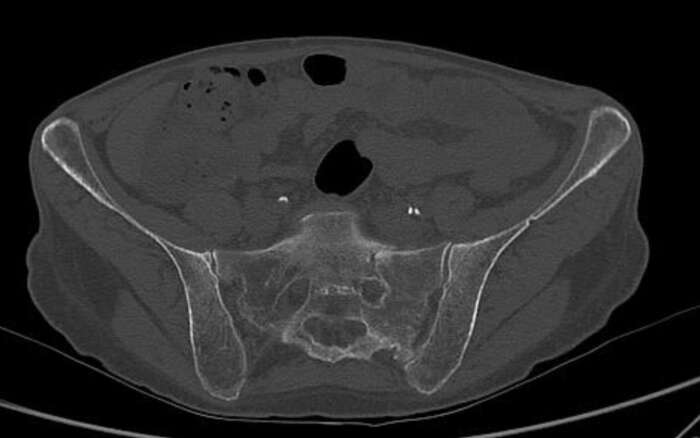

In diesem Beispiel war die Patientin vier Wochen nach einem Sturz nur noch mit Krücken und mit Schmerzen mobil. Die Computer Tomographie (CT) zeigte einen nicht verschobenen Bruch des Kreuzbeins und eine leicht verschobene Fraktur des Schambeins. Während der Operation implantierten wir CT-gesteuert zwei 7,3-mm-Schrauben. Die Schrauben gingen durch beide Ilio-Sakralgelenke und erste und zweite sakrale Wirbelkörper. Die Patientin konnte am nächsten Tag nach Hause entlassen werden und war schmerzfrei mobil.

Fraktur der linken Seite des Sakrums auf Höhe von S1